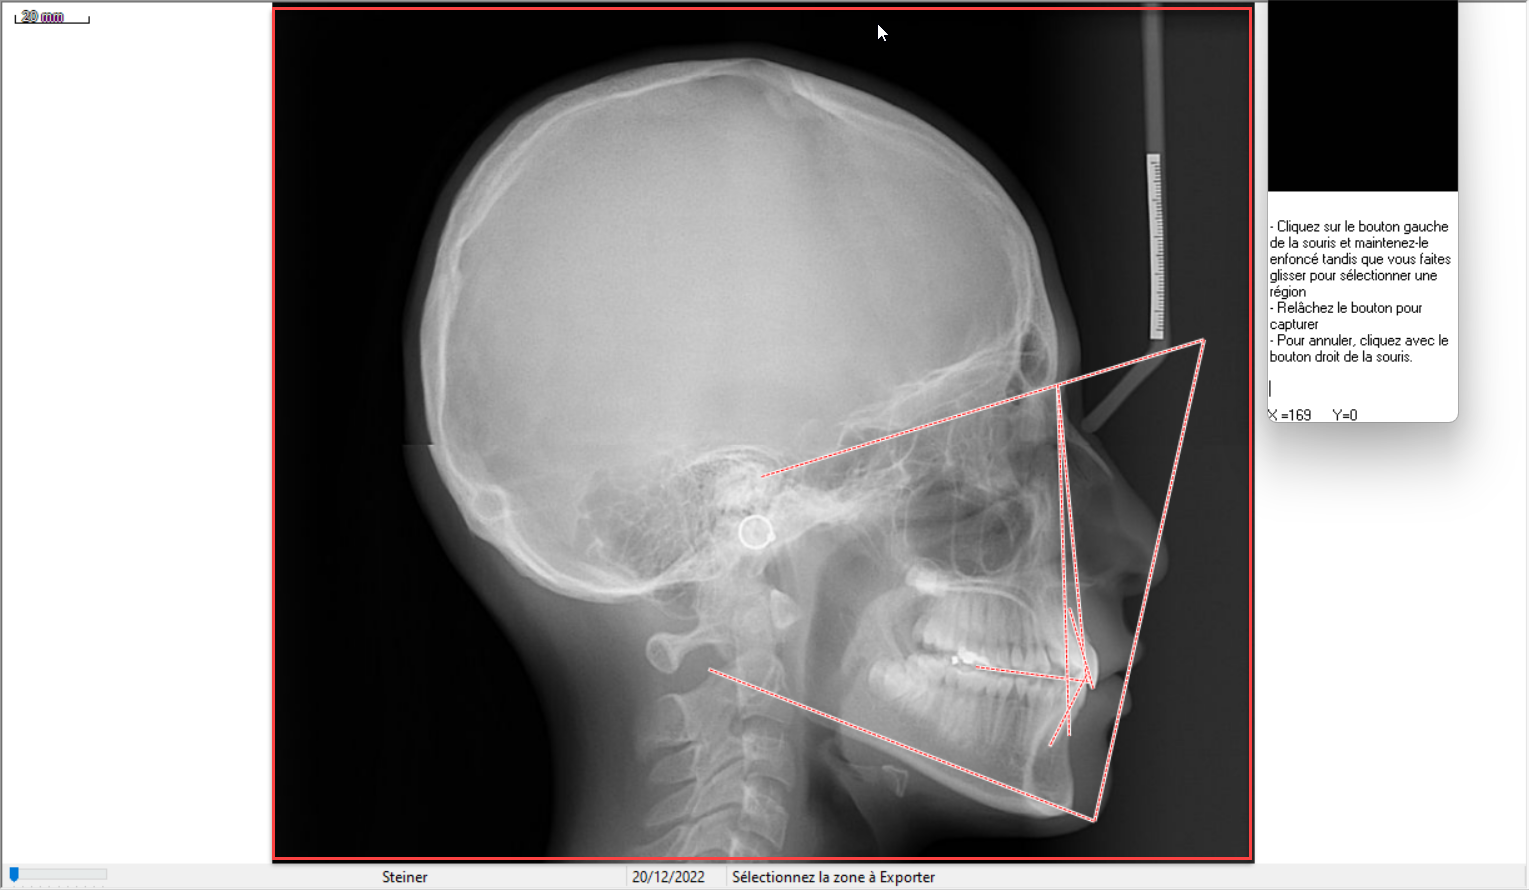

Dans cet exemple d'analyse Steiner, le logiciel demande de capturer (ici le cadre rouge) la radio avec les tracés superposés. Ensuite il vous affiche le tableau comme ci-dessous:

Cliquez sur Enregistrement photo.

Vous retrouverez votre tableau sous forme d'une photo dans votre iconographie à la date du jour.